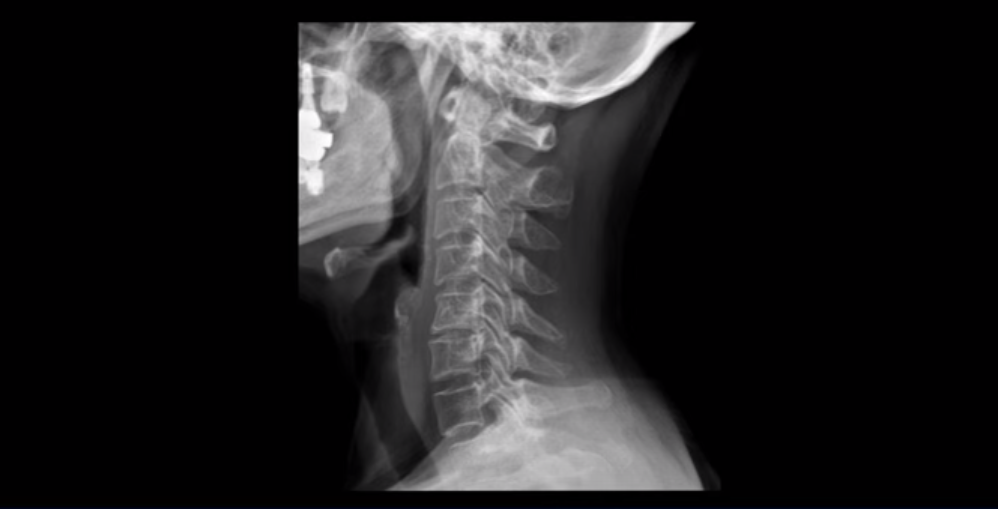

이 환자분은 원인을 알 수 없는 두통, 어지럼증, 메스꺼움, 눈 통증, 눈 침침함, 이명, 팔 통증 팔힘빠짐, 안면 감각 이상과 함께 극심한 목 통증과 어깨통증, 견갑골 통증을 3년 이상 겪으셨습니다. 이런 복합 증상들은 거북목으로 인해 목 근육, 특히 목 앞쪽 근육이 극심하게 뭉칠 때 나타나는 증상입니다. 이런 여러 가지 증상이 나타나는 이유는 거북목으로 인해 극심한 목 근육 뭉침, 특히 목 앞쪽 근육의 단축과 뭉침이 지속되면 목 근육 사이를 통과하는 목 주변의 혈관과 신경에 큰 영향을 미치기 때문입니다. 이 환자분은 고개를 숙이면서 하는 일을 오래하셨고, 그런 이유로 거북목으로 인한 목 앞쪽 근육 및 목 뒤쪽 근육 뭉침 모두 매우 심한 상태였습니다.

일반적으로 환자분들이 어지럽고 두통도 있고 하면 보통 이비인후과나 신경과에 많이들 가시는데, 목 문제 때문에 아픈 사람들은 당연히 이비인후과에서는 이상이 없다는 얘기를 듣고 또 신경과에서도 아무 이상이 없다고 듣거나 혹은 후두신경통을 진단받는 경우가 많습니다. 또 만성적으로 목과 어깨 근육이 뭉치면서 목 통증, 어깨통증이 있기 때문에 정형외과나 통증의학과, 한의원 등에 가면 근막통증증후군 같은 진단을 받는 경우도 많습니다. 게다가 이렇게 목이 아픈 환자분들은 척추병원에 가서 MRI를 찍어보면 이 환자분처럼 40세가 넘은 분들은 퇴행성 목디스크가 보이는 경우가 매우 많습니다.

이 환자분도 역시 이렇게 목디스크가 보이기 때문에 척추병원에서 목디스크 때문이라는 얘기를 듣고 신경 주사를 여러 번 맞게 되지만 목디스크 때문에 아픈 게 아니기 때문에 목디스크를 계속 치료해봐야 좋아지지 않는 겁니다.